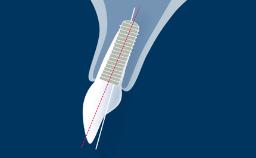

Introduction to Implant Dentistry

Timing of Implant Placement after Tooth Extraction

Learning Module